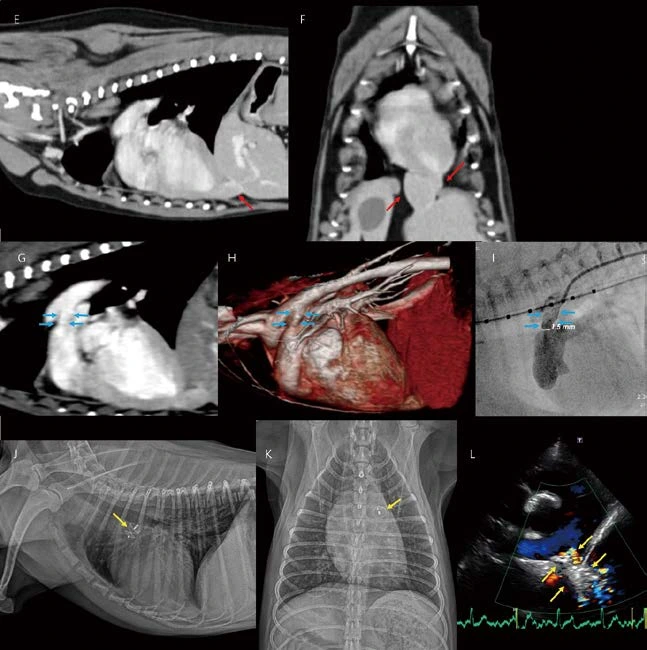

1살 수컷 3.8kg Pomeranian이 잠복고환 중성화수술로 의뢰되어 내원하였습니다. 특별한 임상 증상 없이 건강 상태, 혈액 검사 모두 정상이었으나, 좌측 심장 앞쪽에서 continuous machinery murmur가 청진 되었습니다. 흉부방사선 검사에서 경등도의 둥근 심비대 및 pulmonary overcirculation(외측상에서 cranial lobar vessels, 복배상에서 basal lobar vessels의 확장 소견)이 관찰됩니다(A, B). 복배상에서 대동맥과 폐동맥 사이 정상적으로 관찰되어야 하는 valley가 filling되어 관찰되고, 전형적인 PDA(Patent ductus arteriosus)의 특징, 즉 3 bumps(Aortic aneurysmal bulging, MPA bulging, Lau bulging)가 확인됩니다(B, 노란 화살표). 또한 외측상에서 심음영의 caudoventral contour와 횡격막 사이에서 연조직 밀도의 작고 둥근 결절성 음영이 관찰됩니다(A, 붉은 화살표). 심초음파에서 대동맥과 폐동맥 사이 PDA region이 관찰됩니다(C, 별표). Color Doppler와 CW에서 Duct를 통한 continuous positive flow가 주폐동맥의 anterior wall 따라 Coanda effect를 보이며 관찰됩니다. Peak velocity는 4.5m/s 이상으로 유의적인 pulmonary hypertension 없는 Lto R shunt 상태로 확인됩니다(C, D). Minimal ductal diameter가 대략 2 3mm-로 측정됩니다(C). 이 외 다른 선천적 심장 기형 소견은 관찰되지 않습니다. 심장과 횡격막 사이 작은 연조직밀도의 음영은 심막 내 간엽의 일부로 생각됩니다. PPDH(Pericardioperitoneal diaphragmatic hernia)가 고려되어, PDA와 함께 정확한 진단 평가를 위해 CT 검사를 진행하였습니다. CT 검사에서 간엽 일부가 심막 내로 herniation되어 관찰됩니다(E, F). PDA 지점도 잘 관찰되며, canine angiographic classification 기준으로 type 2A(ductus의 proximal portion의 직경이 지속적으로 유지되다가, pulmonary artery로 진입하는 지점에서 급격히 좁아지는 형태)로 확인됩니다(G, H). 보호자님의 선택에 따라 임상증상이 없는 PPDH는 교정하지 않고, PDA 중재적 시술과 잠복고환 수술만 진행하였습니다. 혈관조영술은 PDA 위치까지 카테터를 삽입하고, selective하게 조영제를 주입하기 때문에 CT보다 훨씬 정확하고 세심하게 minimal ductal diameter(or pulmonary ostium diameter), ampulla diameter에 대한 정보를 얻을 수 있습니다(I). 환자는 PDA plug를 삽입하고 시술을 종료하였습니다. 시술 후 경흉부심초음파에서 PDA plug 주변으로 미약한 residual flow가 남아 있었지만(L), 서서히 개선되어 치료 종료하였습니다. 흉부 방사선 검사에서 PDA plug는 잘 위치해 있고, 심비대, pulmonary overcirculation이 개선되어 관찰됩니다(J, K).

이 환자 역시 PDA, L to R 환자입니다. 경흉부심초음파에서는 canine PDA angiographic classification 을 바탕으로 type 2A로 생각되었으나, 실제 경식도심초음파(A, B)와 혈관조영술 모두에서 Type 3(ductus 직경의 실질적인 감소(<20%)가 없는 tubular 형태)로 확인되었습니다. PDA occluder failure 위험도가 높아 surgical ligation을 실시하였고, any complications 없이 치료를 종료하였습니다.

Catheter based occlusion 시술에서 반드시 필요한 것은 아니지만, 경식도심초음파를 이용하게 되면, 보다 세밀한 정보를 실시간으로 얻을 수 있습니다. 다음 환자에서도 경식도심초음파를 통해 PDA type및 직경 평가(A), 카테터 진입 및 적절한 위치 평가(B, 붉은 화살표), 실시간 혈류 평가(A, 시술 전, C duct , occluder 장착 후), duct occluder의 정확한 위치 및 안정성 평가(D, E 파란 화살표) 등의 세밀한 정보를 catheter based occlusion 시술과 동시에 실시간으로 얻을 수 있었습니다.

이 환자는 surgical ligation을 진행한 환자입니다. 흉부방사선 검사에서 cardiomegaly, 3 bumps, pulmonary overcirculation이 관찰되었고(A, B), 심초음파, bubble study에서 isolated L to R PDA(C, D)가 확인되었습니다. 또한 폐동맥 판막 후방에서 Duct를 통한 continuous positive flow가 주폐동맥벽을 따라 심한 와류를 보이는 지점에서 flap(E, 붉은 화살표, 동영상으로 보면 pulmonic valves와 별도로 펄럭이는 flap이 명확히 관찰)이 관찰됩니다. Pulmonary arterial dissection(폐동맥 박리) 상태로 생각됩니다. Pulmonary regurgitation, tricuspid regurgitation의 peak velocity는 subclinical하였고, 우심 확장 비후 소견은 관찰되지 않으므로, Pulmonary hypertension 보다는 PDA에 의한 pulmonary aneurysmal dilation이 원인일 것으로 생각되었습니다. Surgical ligation 또는 중재적 시술 교정 방법에 있어서 보호자님의 선택으로 수술적 교정을 실시하였습니다. 다행히 출혈없이 수술은 매우 조심스럽게 마무리되었고, 수술 후 심초음파에서 폐동맥 판막 후방 dissection 소견은 지속적으로 관찰되지만 PDA는 잘 교정된 것으로 확인되었으며, 환자도 continuous machinery murmur 없이 양호한 상태로 잘 지냈습니다. 그러나, 2주 후 급성 기력 저하로 응급 내원하였고, 심초음파에서 PDA 수술 부위 인접한 폐동맥벽에서 dissection이 추가적으로 확인되었습니다(F, 노란 화살표). Pedunculated하게 움직이는 혈전 음영(F, 파란 화살표)도 관찰되었습니다. 이 위치에서 심한 와류 flow가 다시 관찰되었습니다. 안타깝게도 환자는 한 달 뒤 폐렴으로 사망하였습니다.

이 환자 역시 흉부방사선 검사에서 cardiomegaly, pulmonary overcirculation, 3 bumps(A, B), 심초음파, bubble study에서 isolated L to R PDA (C, D)로 확인되었습니다. 심초음파에서 pulmonary arterial dissection(E) 소견이 함께 관찰되어, 그렇지 않은 환자에 비해 수술/시술의 위험 가능성에 대해 고지하였더니, 보호자님이 내과적 모니터링을 선택하셨습니다. 약 1년 뒤 졸도 증상으로 응급 내원하였고, 흉부방사선에서 심비대 with 3 bumps는 여전히 관찰되나, 1년 전과 비교 시 pulmonary overcirculation은 관찰되지 않습니다(F, G). Pulmonary overcirculation 여부는 환자 상태를 평가하는데 중요한 포인트가 될 수 있습니다. L to R PDA와 달리 Reverse PDA에서는 pulmonary hypoperfusion 상태를 보여줍니다. 심초음파에서 우심방, 우심실, 주폐동맥의 확장, 우심실벽 비후, ductal continuous positive flow의 소실, Severe TR, PR이 관찰됩니다(H, I, J). 환자는 Reverse PDA 상태로 진단되었고, 단기간에 다량의 복수를 비롯한 우심부전이 진행되어 내과적 management에도 불구하고 3개월 내로 사망하였습니다.